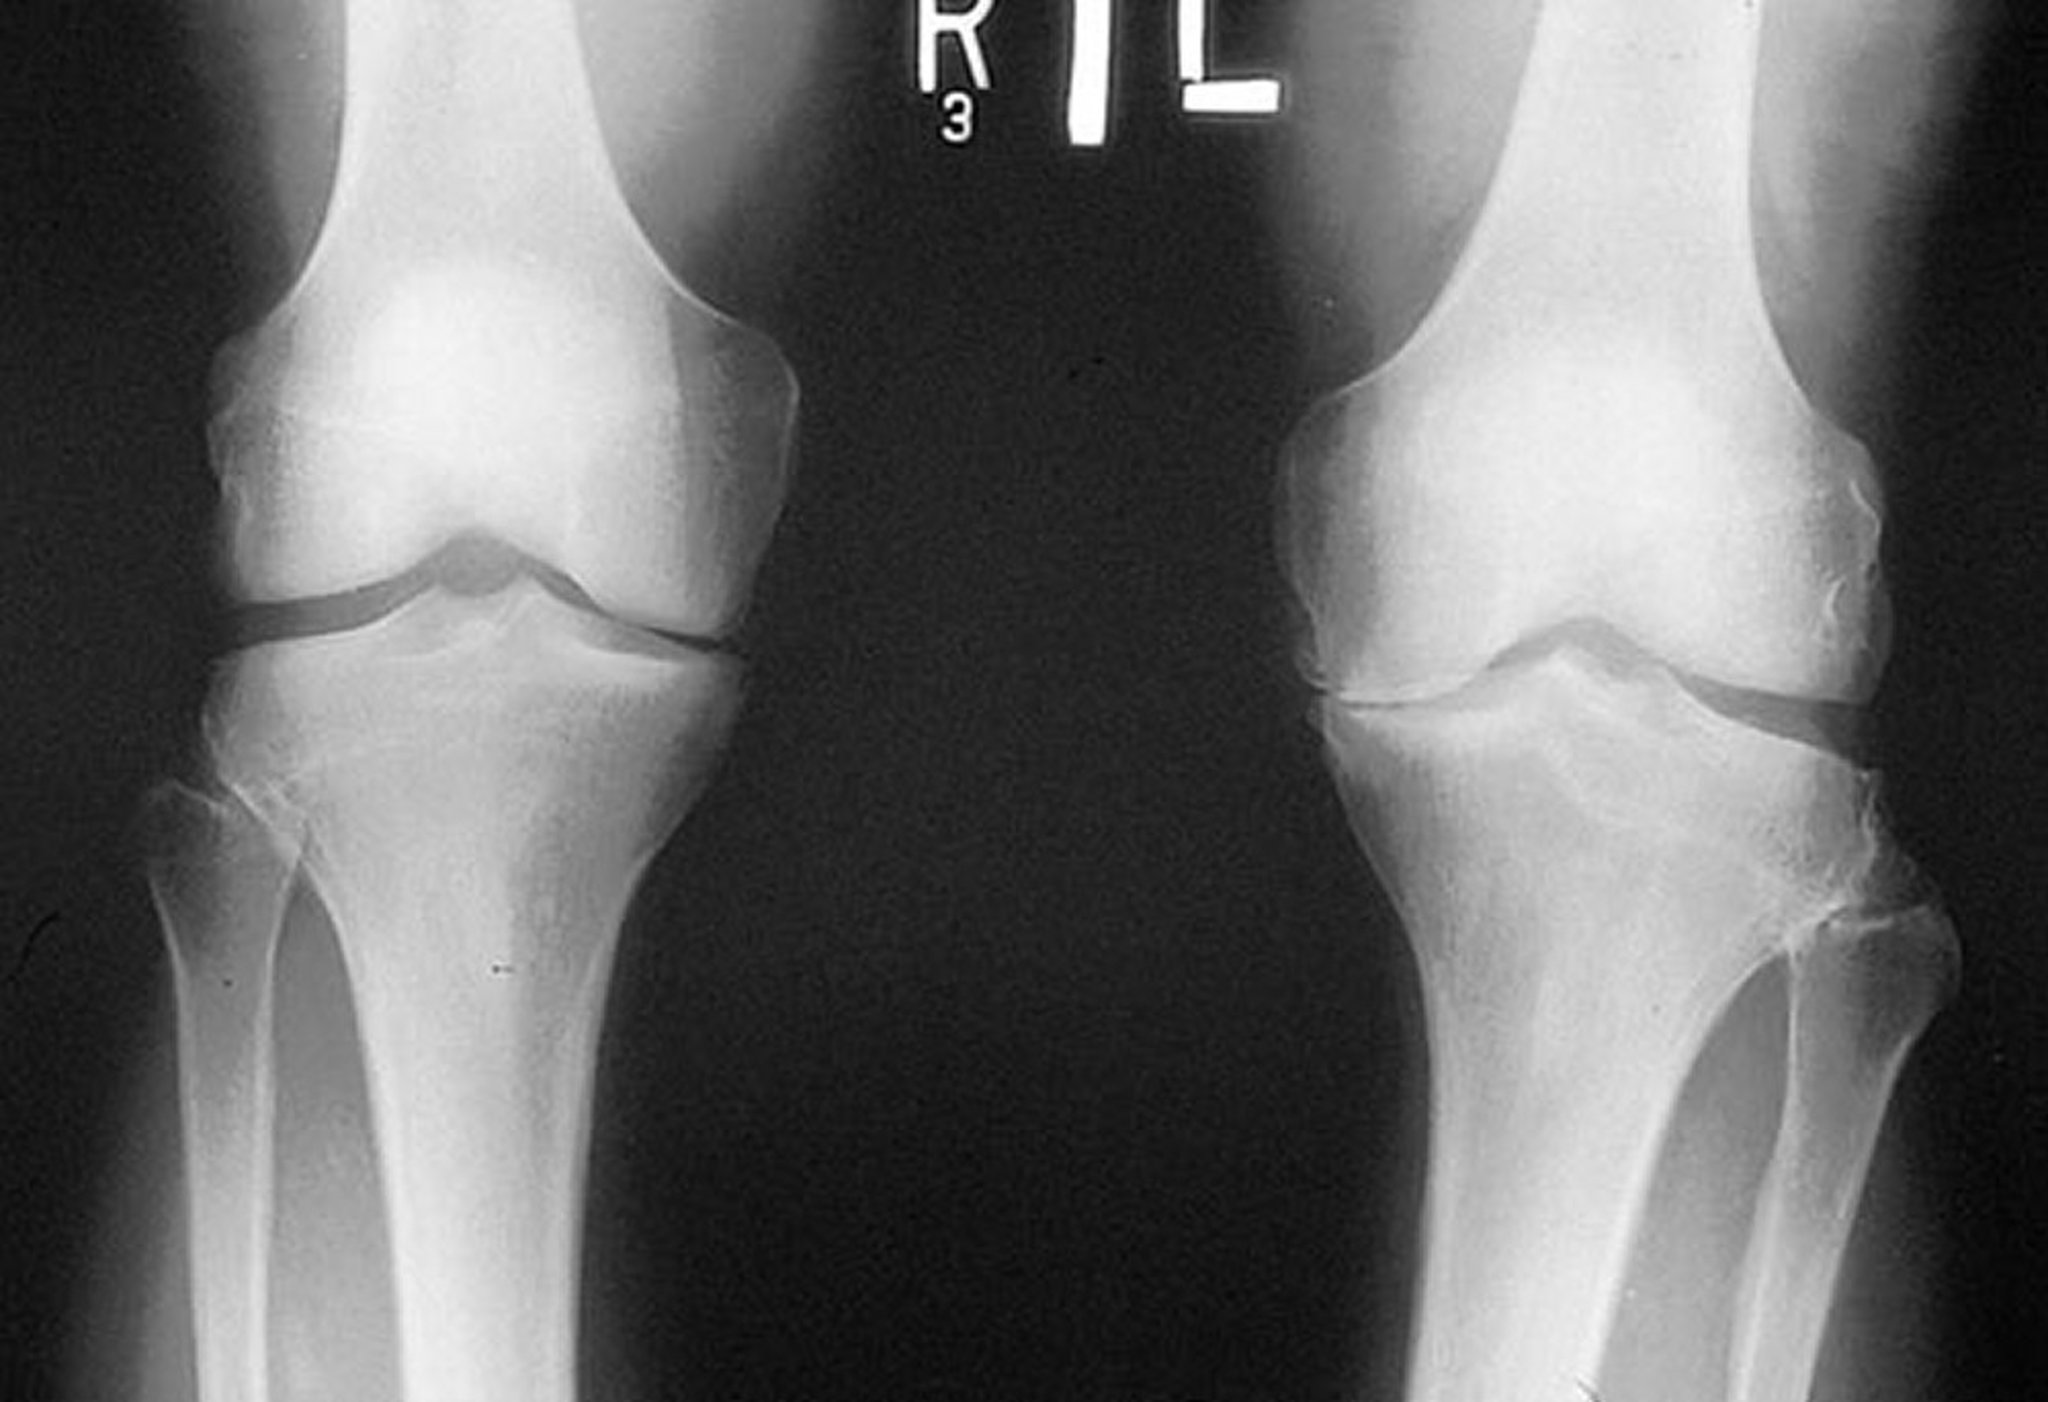

Radiograph of the Knee in Osteoarthritis

This radiograph, taken while the patient is standing, shows that the tibiofemoral joint space in the medial compartment of both knees is narrow, particularly on the left. Marginal osteophytes are visible. There is attrition of the left medial tibial plateau.